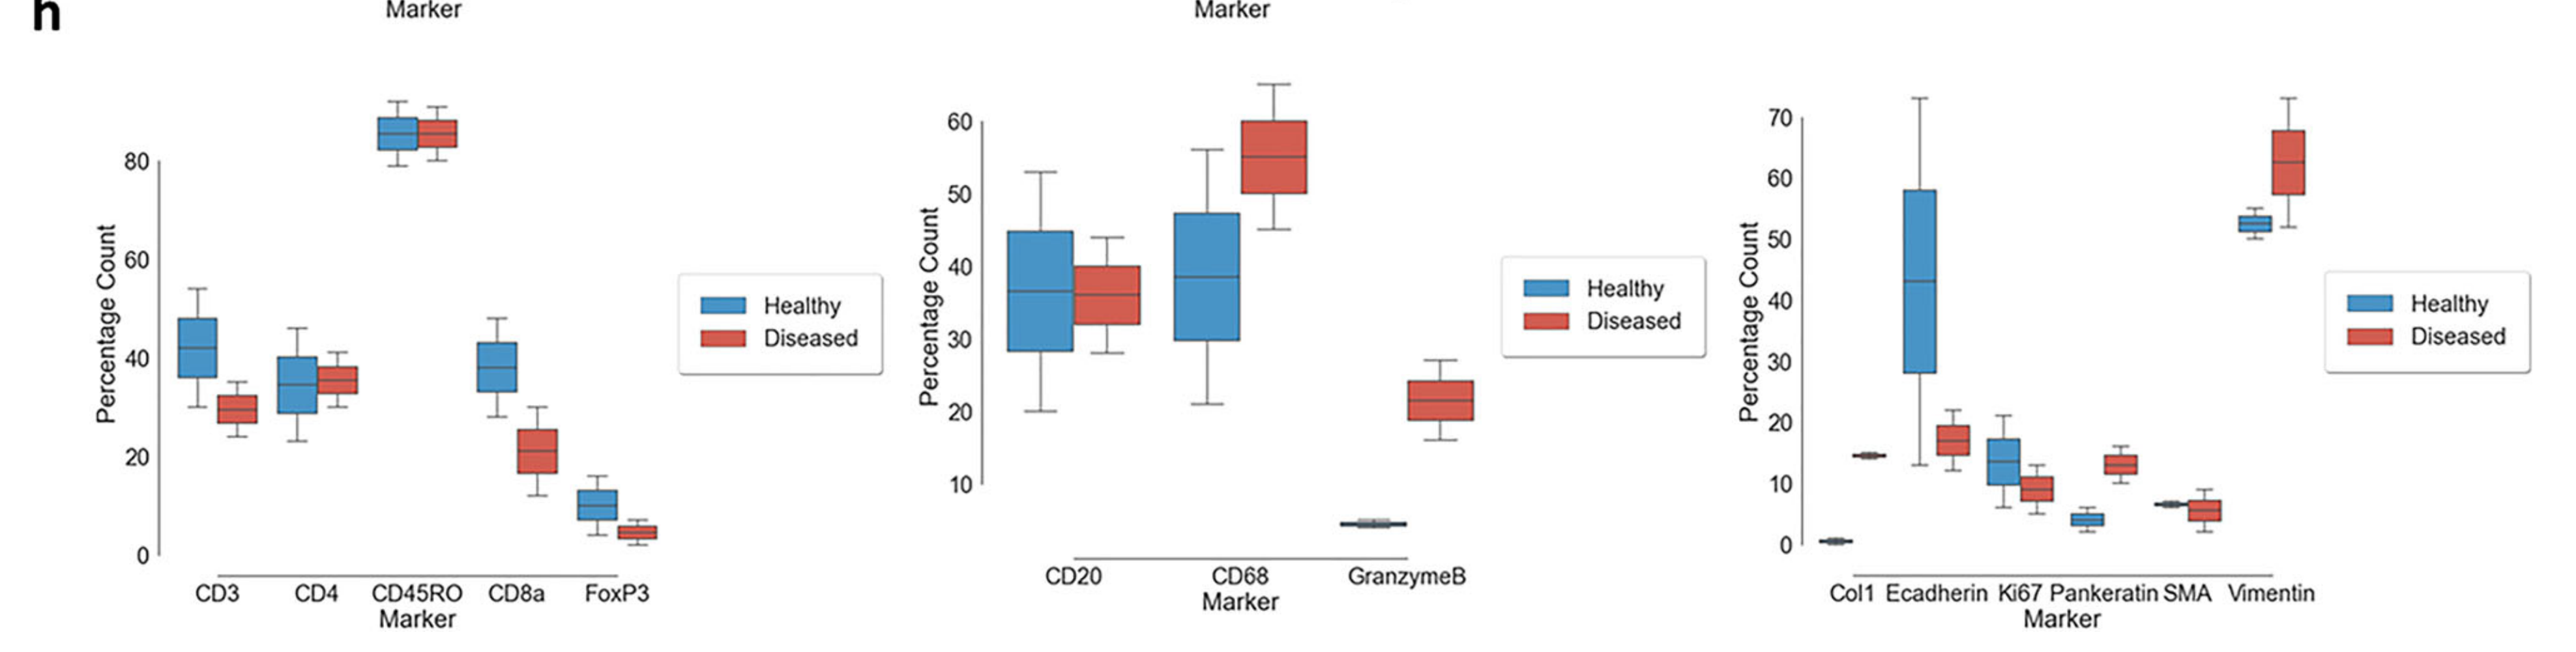

Li X. et al. - 2025

SPEX: A modular end-to-end platform for high-plex tissue spatial omics analysis

Condition Dimension

Categorical

Data Components

Biological AnnotationGene Expression Matrix

Metadata

None

Modality

Proteomics

Resolution of observation

Cellular

Visualized Elements

Statistic

How does expression of a gene differ across patient categories?

Biological

Molecular

Abstraction

Complete

Chart Type

Boxplot

Communicative/Contextualization

Annotation

Comparative Design

Juxtaposition

Layout

Linear

Scalability Strategy

Summay/Aggregate